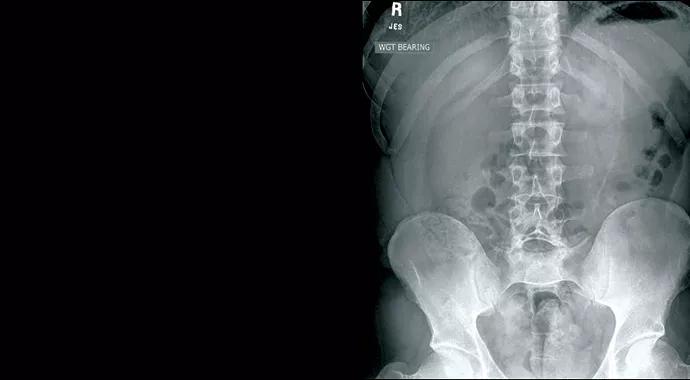

Standing anteroposterior and lateral lumbar radiographs (Figure 1) help define any underlying alignment concerns that may be missed on studies while the patient is lying down. Spondylolysis can be appreciated on oblique lumbar radiographs. Advanced imaging studies (MRI, CT, and bone scan with SPECT) can provide greater detail and help determine the treatment course.

Figure 1. Anteroposterior (left) and lateral (right) lumbar radiographs in a patient with defects of the pars interarticularis at L5 with spondylolisthesis of L5 on S1. The patient was treated successfully without surgery.